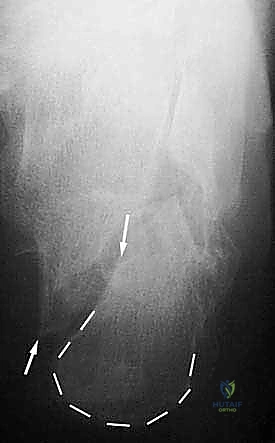

- دمج المفصل تحت الكاحل (Subtalar Arthrodesis):

في الغالبية العظمى من حالات سوء الالتئام، يكون المفصل تحت الكاحل قد تدمر تماماً بسبب الخشونة والاحتكاك. الحل الجذري والنهائي للألم هنا هو "دمج" أو "تثبيت" هذا المفصل. يقوم الدكتور هطيف بتنظيف الغضاريف التالفة بالكامل، ووضع العظام في وضعها التشريحي الصحيح، ثم تثبيتها باستخدام براغي معدنية قوية جداً (Screws) لتلتحم وتصبح عظمة واحدة صلبة خالية من الألم.

- يتم إجراء أشعة سينية للتأكد من بدء التئام العظام والتحام المفصل.